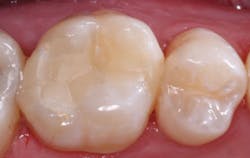

Additional clinical time for dentists: A small Class II resin-based composite can usually be placed in a short time, while larger composites require much more time and expertise (figure 3). Third-party payers pay the same regardless of the size of the restoration. If lesions are not identified early, the dentist must spend more time preparing the tooth and then placing and finishing the restoration. Not only does the patient suffer shorter restoration longevity, additional future replacement of the restoration, and higher cost, but the dentist also expends more time and effort for a large restoration and receives less proportionate revenue for the services (figures 4a and 4b).

Figures 4a and 4b: The restored premolar tooth is the same premolar shown in Figure 3. Such small restorations serve far longer than large ones as shown in the molar.